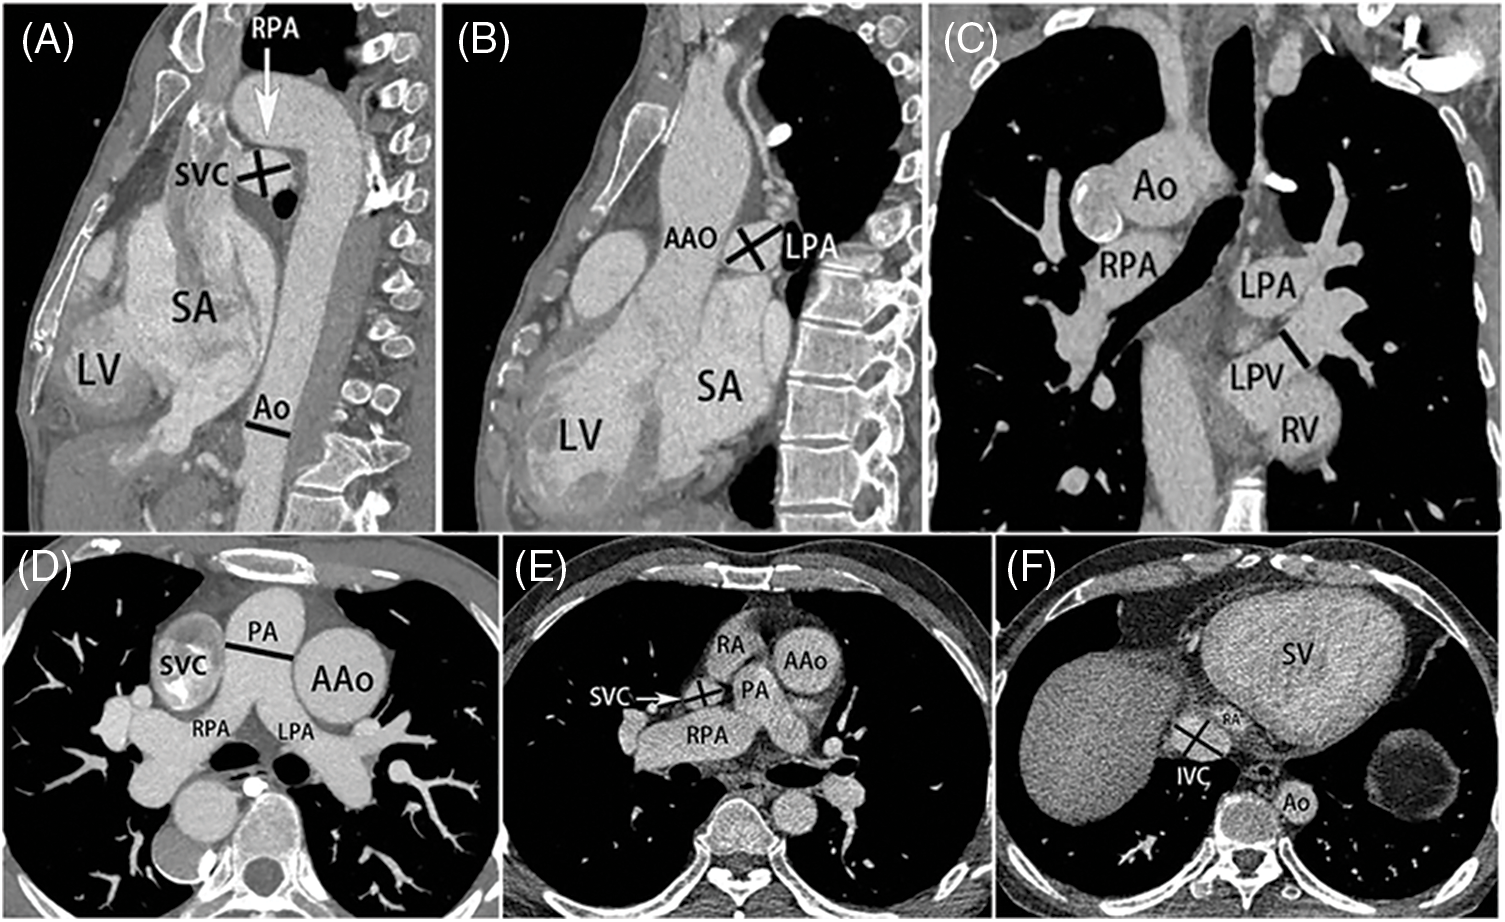

DSCT images were reconstructed into 3D images that were used to measure the diameter and area of the pulmonary artery and vein. The diameter of the descending aorta was measured at the level of the diaphragm (Fig. 1A), and those of the superior and inferior vena cava were measured at the level of the atrium (Figs. 1E and 1F) [17]. The diameters of the pulmonary artery and the pulmonary vein were measured in the sagittal or coronal view. The diameter of the pulmonary trunk was measured at the level of pulmonary bifurcation (Fig. 1D). The left and right pulmonary arterial diameters were measured at 1 cm distal to the bifurcation of the left and right pulmonary arteries (Figs. 1A and 1B). The collateral vessels >2 mm in diameter were measured at the proximal orifices [18]. The diameter of each pulmonary vein before the atrium entrance was also measured (Fig. 1C). The cross-sectional area of each pulmonary vein was calculated assuming that it was round [8,19], the McGoon ratio, PAI, TNPAI and PVI were calculated by the following formula [8,19]:

Figure 1: Measurement diagram. (A) The diameter of the DAo was measured at the level of the diaphragm. (B, C) The diameters of the pulmonary artery and pulmonary vein were measured in the sagittal or coronal view. The left and right pulmonary arterial diameters were measured at 1 cm distal to the bifurcation of the left and right pulmonary arteries. (D) The diameter of the pulmonary trunk was measured at the level of pulmonary bifurcation. (E, F) The diameters of the SVC and IVC were measured at the level of the atrium. SA = single atrium, LV = left ventricle, Ao = aortic, SVC = superior vena cava, RPA = right pulmonary artery, AAo = ascending aorta, DAo = descending aorta, LPA = left pulmonary artery, LPV = left pulmonary vein, RV = right ventricle, PA = pulmonary artery, RA = right atrium, SV = single ventricle, IVC = Inferior vena cava